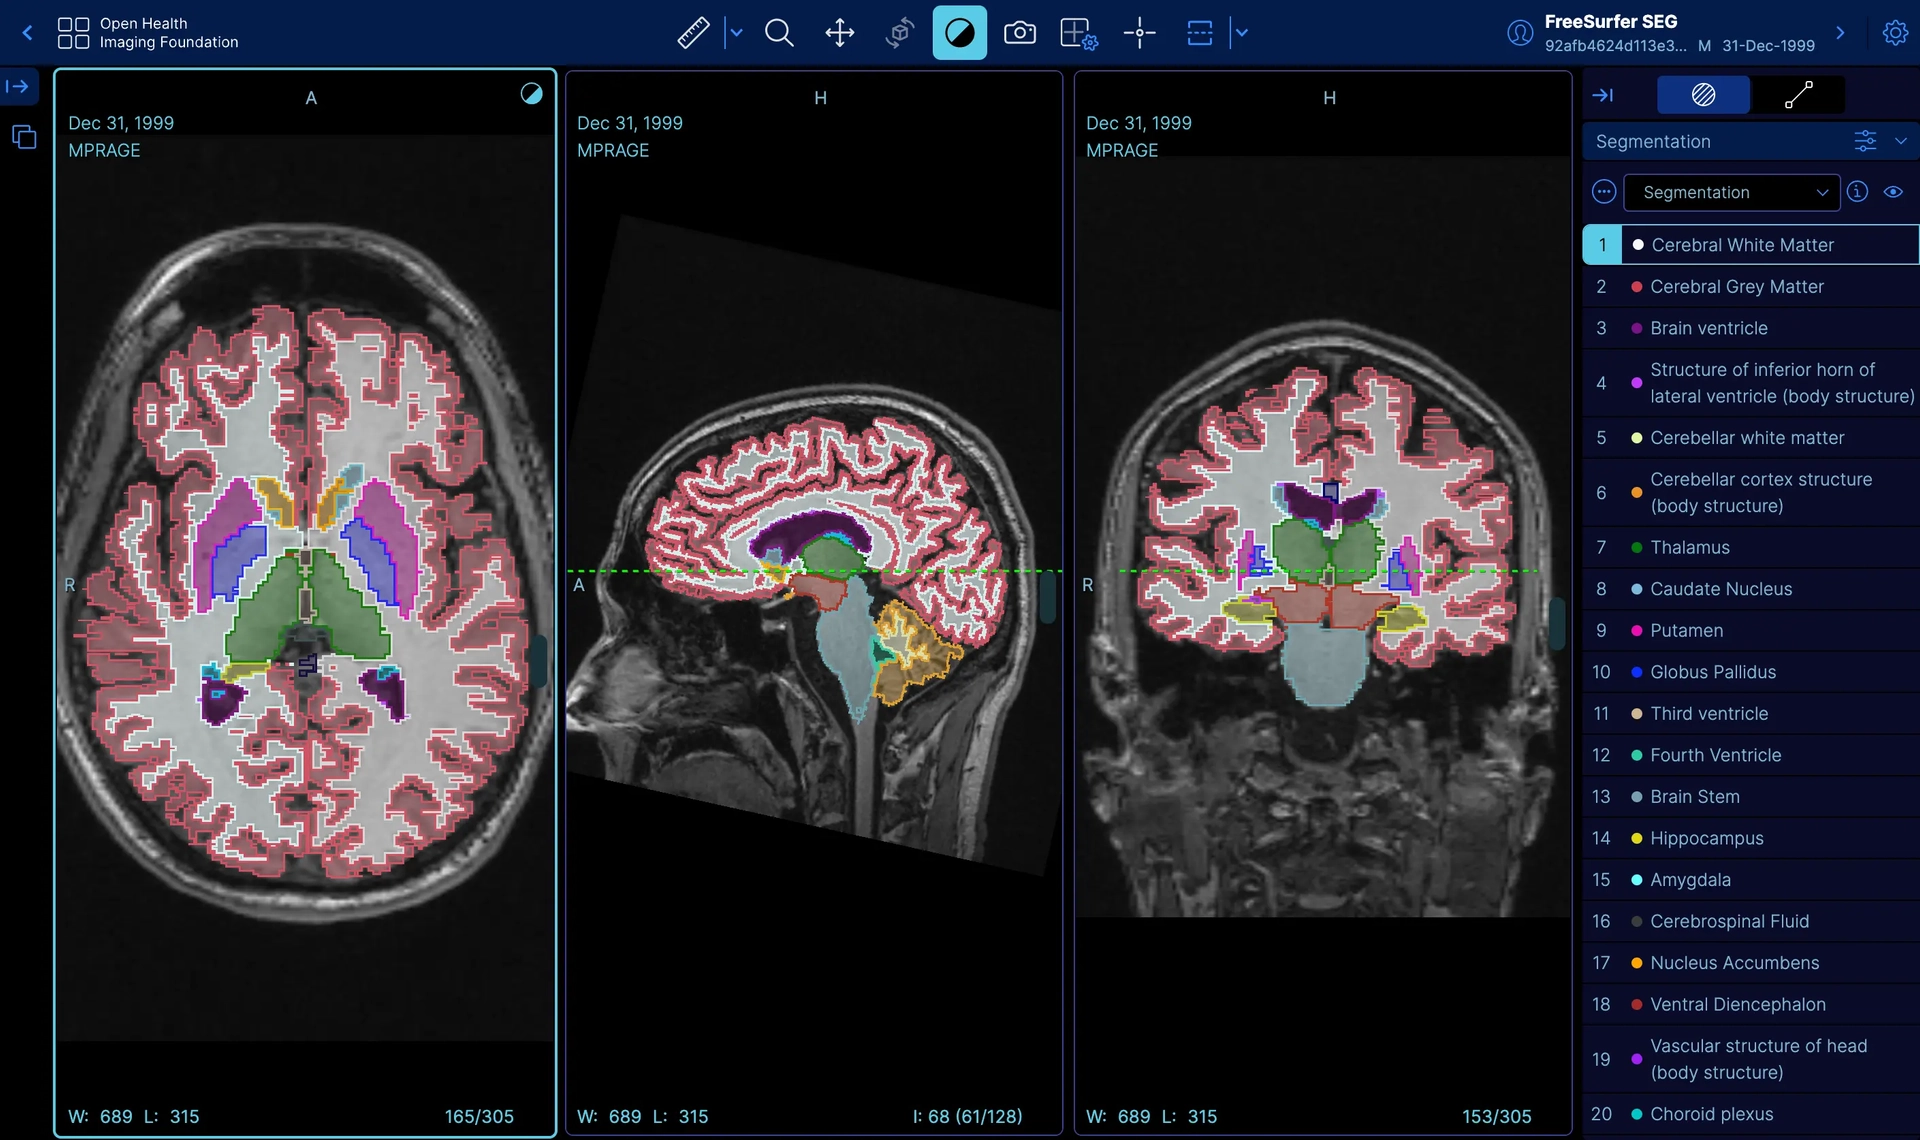

Web Viewer รองรับ MPR, Window/Level, Annotation ออกแบบตาม Workflow ของคุณ

ผสาน AI Model เข้ากับ DICOM Pipeline สำหรับ Organ Segmentation, CAD และ Auto-annotation